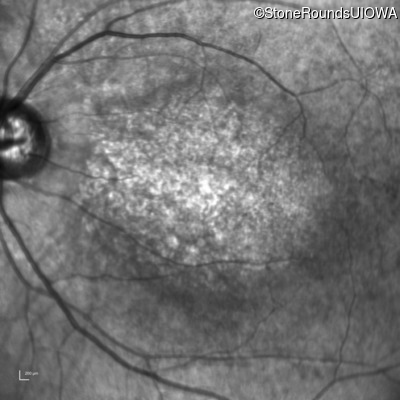

Age at visit: 6 years

OD OS

This 6 year old male first experienced a loss of visual acuity at age 5. His acuity was previously normal. He is otherwise healthy.